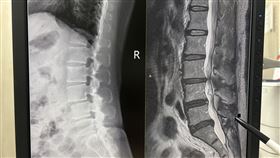

脊椎特材「健保幫付20%」省9萬 萬人受惠

健保會近期通過「特殊功能/材質脊椎間體護架(CAGE...